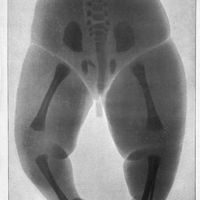

0057 - Page 51 - Obstétrique. Tératologie

0059 - Planche V - [Planches]

0071 - Page 63 - Obstétrique. Radiographie obstétricale

0074 - Planche VI - [Planches]